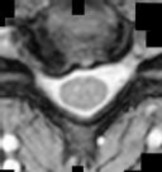

Figures 1 and 2 show sagittal and axial MRI from an 83-year-old woman with an ataxic gait, loss of dexterity, and intermittent loss of bowel and bladder control. The symptoms have been getting progressively worse over the past several weeks.

What disease process is most likely the cause of the patient’s symptoms?

4. Pigmented villonodular synovitis Discussion: B

The patient has a pannus at the C1-2 articulation that is compressing the spinal cord and causing myelopathy symptoms. The development of a pannus at this location has been associated with rheumatoid arthritis. Steinberger and associates showed increased morbidity and mortality when using an anterior approach and the surgery took longer than 4 hours. Chieng and associates showed better outcomes and lower complications rates using a posterior approach.

Question 12 of 100

CLINICAL SITUATION

When discussing anterior versus posterior surgical techniques, you counsel this patient that

Discussion: A